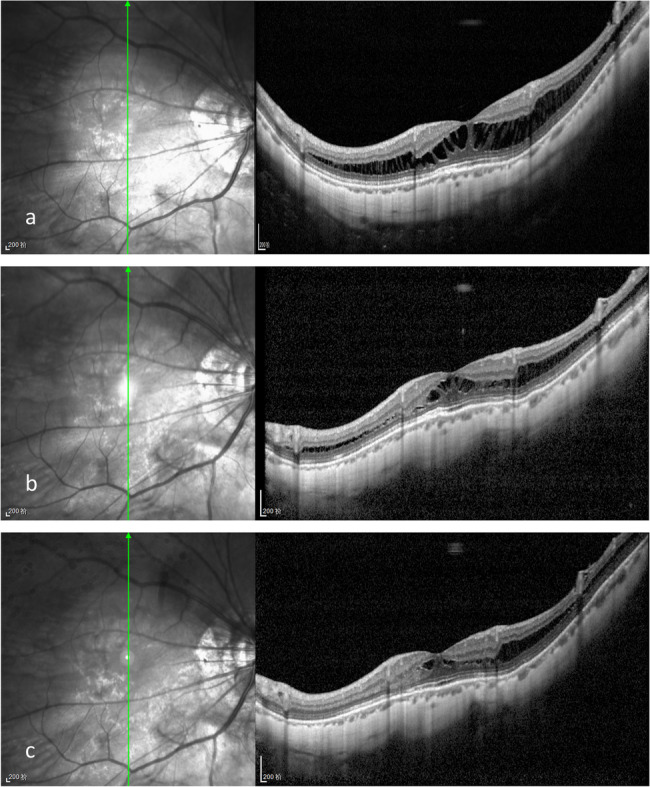

Background: To observe the safety and efficacy of posterior scleral reinforcement (PSR) with a bovine pericardial patch in patients with progressive high myopia over a 1-year follow-up period.

Methods: Thirteen eyes of 11 patients with progressive high myopia who underwent the PSR surgery were followed up with measurements of axial length (AL), spherical equivalent (SE), best corrected visual acuity (BCVA), and intraocular pressure (IOP) at baseline, 1 and 3 months, and 1 year postoperatively.

Results: The preoperative AL (29.55 ± 1.43 mm) was decreased to 28.95 ± 1.48 mm at 1 month post-PSR surgery and elongated to 29.68 ± 1.45 mm at the end of the follow-ups. The SE decreased from - 15.13 ± 3.43 diopters (D) preoperatively to - 14.43 ± 4.07D at 1 month post-PSR surgery and increased to - 15.25 ± 3.08D at the end of the follow-ups. BCVA remained relatively stable, with no statistically significant differences observed during the 1-year follow-up. The postoperative BCVA improved in eight eyes (62%). No serious postoperative complications were observed.

Conclusions: The modified Snyder-Thompson PSR surgery utilizing a bovine pericardial patch has the potential to delay AL elongation over a one-year postoperative period.